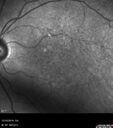

70-year-old Left eye worse than the right. Both eyes see distortion in the amsler grid for a few months

HTN, High Lipids, Osteoporosis

Meds: Lutein once daily, Calcium, Fish oil, Red Yeast Rice, CoQ10, Magnesium, MVI, Xanax

VA 20/16 OU

2+NS cataract